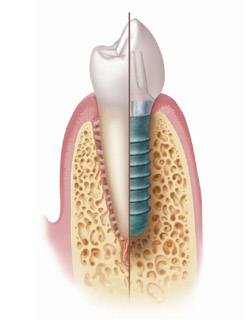

¿Qué es un implante?

Los implantes dentales son dispositivos que, insertados en el hueso, funcionan o actúan como una raíz artificial, soportando así la futura corona protética por medio de un aditamento intermedio conocido como pilar.

Consideraciones tras la colocación de los implantes

El concepto de osteointegración u oseointegración se define como la conexión directa, estructural y funcional entre el hueso y la superficie del implante durante las cargas funcionales o masticatorias. Este fenómeno dependerá de la capacidad de cicatrización, reparación y remodelado de los tejidos, tanto del hueso como de la encía. Así, para poder establecer un pronóstico predecible, la manipulación y cuidado meticulosos de los mismos resulta clave para poder hablar de éxito clínico.

Los implantes como medio para una prótesis

Una vez respetado el período de cicatrización, se llevará a cabo la restauración protética, esto es, conectar el implante osteointegrado a una corona a través de un elemento intermedio conocido como pilar. Este procedimiento puede realizarse de manera atornillada o cementada.